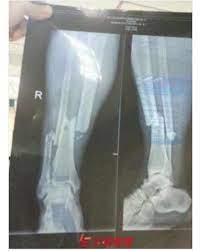

Demba Ba Striker Asks Did We Win As He Wakes Up In China Hospital After Horrific Leg Break Before Undergoing Surgery This Weekend

Demba Ba Suffers Potentially Career Ending Leg Break During Chinese Super League Game

Former chelsea and newcastle striker demba ba endured a terrible damage in the chinese super league's shanghai derby on sunday. Demba ba is the f*cking man, said one account, accompanying its post with the footage of veteran ba pointing his finger. [view the story fans react to demba ba. This is the injury history of demba ba from istanbul büyüksehir belediyespor. I won't call time on my career, that's for sure, said ba, 31. In the game fifa 21 his overall rating is 73. Former teammates cesar azpilicueta and john terry both took to instagram on sunday to show their support for ba. Başakşehir, demba ba'nın sözleşmesini tek taraflı olarak feshetti.

Последние твиты от demba ba (@dembabafoot). Fans were divided amid the confusion, with some calling the scenes disgusting if true and others questioning whether basaksehir should have walked off. Süper lig'in son şampiyonu medipol başakşehir, demba ba ile yollarını ayırdı. Fa cup 4th round replay. Shanghai shenhua striker demba ba suffered a broken leg against shanghai sipg on july 17, but he remains positive the incident won't end ba posts instagram clip after surgery. The former west ham, newcastle and chelsea forward added. This is the injury history of demba ba from istanbul büyüksehir belediyespor. Demba ba horrific injury breaks leg demba ba horrific leg break vs shanghai sipg 17072016. Injury history, suspensions and absences are based on a variety of media reports and are researched with the greatest of care. Demba ba'nın medipol başakşehir kariyeri sona erdi. Demba ba (born 25 may 1985) is a professional footballer who plays as a striker for turkish club i̇stanbul başakşehir and the senegal national team. Başakşehir, demba ba'nın sözleşmesini tek taraflı olarak feshetti. Demba ba, fenerbahçe maçında kadroya alınmamıştı.